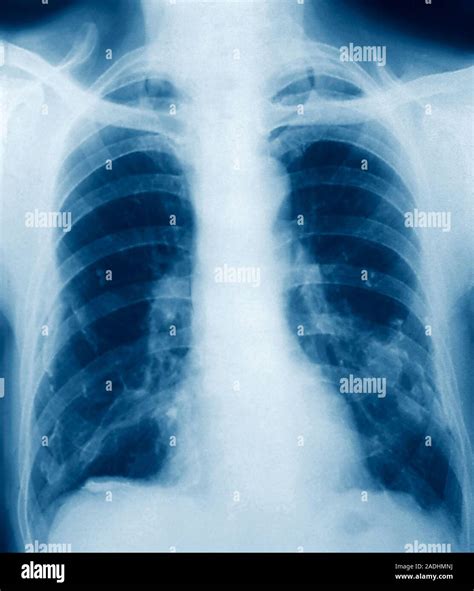

• Chest X-ray: A chest X-ray can reveal the presence of calcium deposits in the lungs.

• CT Scan: A computed tomography (CT) scan provides detailed images of the lungs and can help identify the location and extent of the calcification.